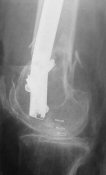

KEMMD> method of treatment for distal femur fractures

A new toy is more interesting and fashionable. And anyway it is not panacea, i have already seen presentations with LISS failures like the attached one presented by D.Seligson. And people also demonstrated incisions say that the method is not so LESS invasive as it supposed to be.